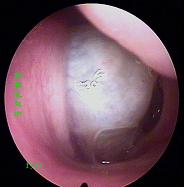

鼻炎长期得不到有效治疗导致鼻息肉以及鼻腔囊肿

一、基本检查:1.前鼻镜检查。2.X线鼻泪管造影,明确有无并发鼻窦感染。出现哪些症状表明诱发鼻窦感染?在线咨询为您详细讲解。